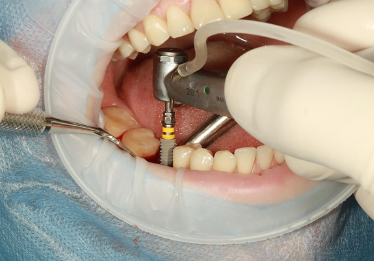

임플란트란 치아가 빠졌을 때 인공치근(임플란트)을 잇몸 뼈에 식립해 자연치아처럼 기능하게 만드는 치료입니다.

자연치에 가까운 기능과 외관을 제공하기 때문에 많은 분들이 임플란트를 선택하고 있습니다.